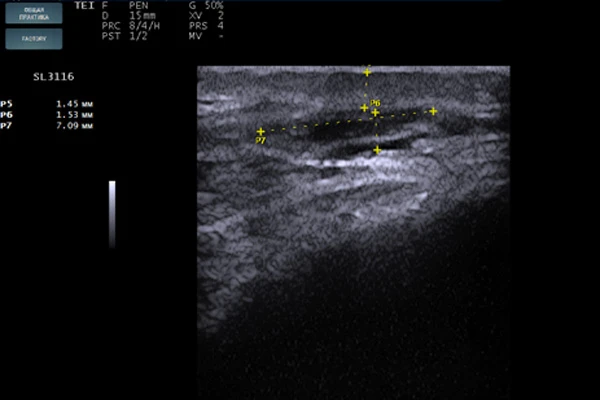

STYLAGE® HydroMax был введен в область губ и периоральной зоны комплектной иглой 30 G в линейно-ретроградной (мезоармирующей) технике. Слой введения — глубокая дерма (Рис. 1). Сразу после введения была выполнена сонограмма в зоне носогубной складки (Рис. 2). На изображении хорошо видны зоны имплантата анэхогенной структуры с ровными краями, овоидной формы, так же заметно, что ткани в этой области сдвинуты по направлению друг от друга и между дермой и мышечным слоем определяется наличие геля. На контрольной сонограмме, сделанной через 4 месяца (Рис. 3), имплант приобретает изоэхогенную структуру, в нем определяются гипоэхогенные включения, что указывает на начало процесса биодеградации и замещение импланта собственными тканями. На сонограмме 3, выполненной через 13 месяцев (Рис. 4), хорошо визуализируется участок локации импланта с границей гиперэхогенной капсулы, внутри которой определяется полное разрешение процесса биодеградации.

Сонограмма дермального имплантата

Рис. 2. Сонограмма дермального имплантата сразу после введения